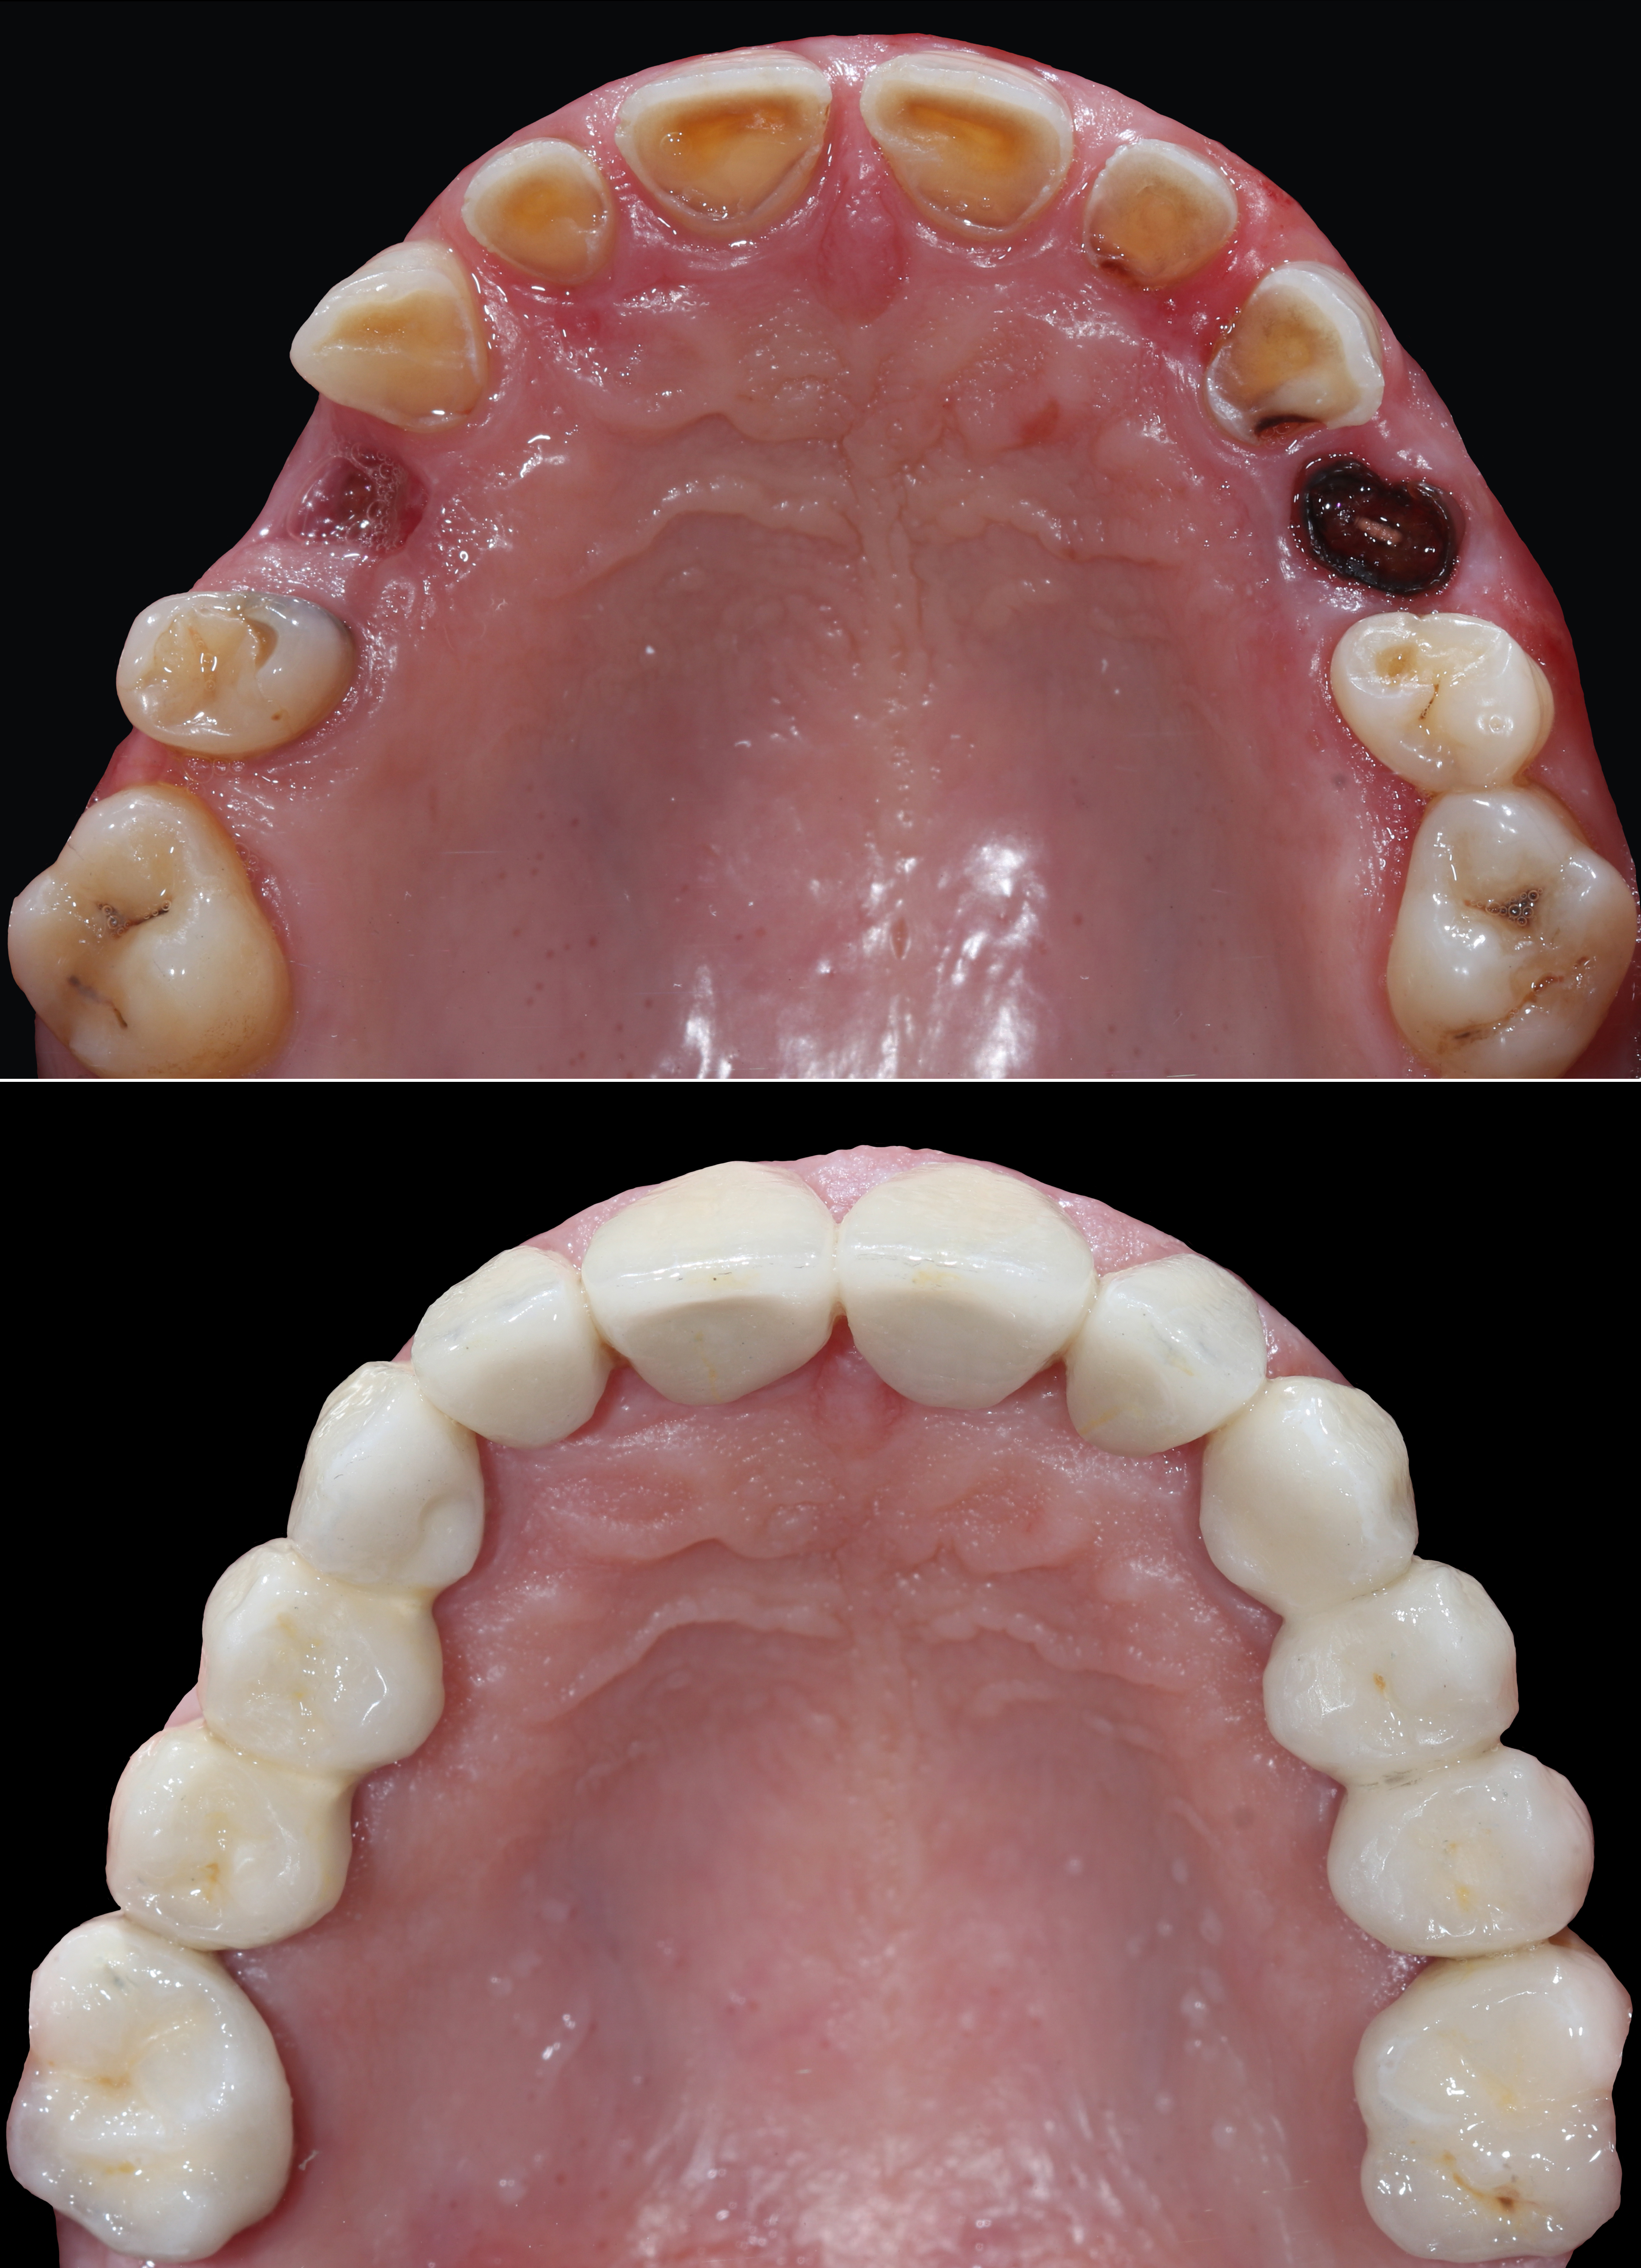

Ολική αποκατάσταση φθαρμένης και αποδιοργανωμένης οδοντοφυΐας με κεραμικές αποκαταστάσεις

Ασθενής με αποδιοργανωμένη, εκτενώς φθαρμένη οδοντοφυΐα, τερηδόνες και κατεστραμμένα δόντια στην άνω γνάθο που προκαλούσαν έντονους πόνους, προσήλθε στο Aesthetic Dental Studio στην Καλαμάτα με στόχο την αισθητική και λειτουργική αποκατάσταση του στόματός της.

Σε πρώτη φάση, αφαιρέθηκαν τα δόντια που ήταν πλήρως κατεστραμμένα, πραγματοποιήθηκαν ενδοδοντικές θεραπείες στα δόντια που μπορούσαν να αποκατασταθούν και έγιναν εμφράξεις σε δόντια με απλή τερηδόνα. Έτσι, το στόμα σταθεροποιήθηκε και ήταν πλέον έτοιμο για την δεύτερη φάση της θεραπείας, που περιελάμβανε την προσθετική αποκατάσταση των δοντιών.

Αφού όλα επιβεβαιώθηκαν, έγινε λήψη ψηφιακών αποτυπωμάτων με ενδοστοματικό σαρωτή και στην συνέχεια τοποθετήθηκαν ακίνητες κεραμικές αποκαταστάσεις ολικής επικάλυψης (στεφάνες και γέφυρες).

Το τελικό αποτέλεσμα ήταν αισθητικά άρτιο και λειτουργικά σταθερό, προσαρμοσμένο στις ανάγκες της ασθενούς.